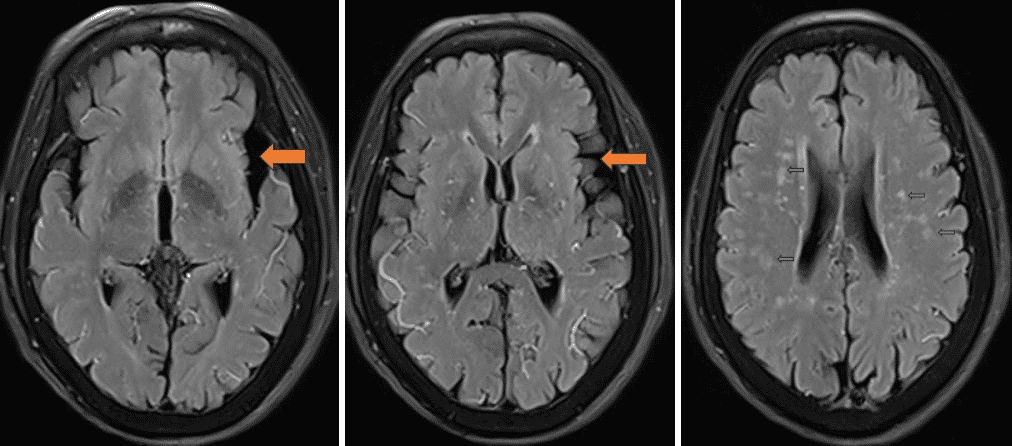

头MR(Flair序列 2023-11-29)可见双侧颞叶萎缩,以左侧为重;双侧侧脑室周围皮层下白质区域可见多发缺血灶及腔隙性梗死灶;